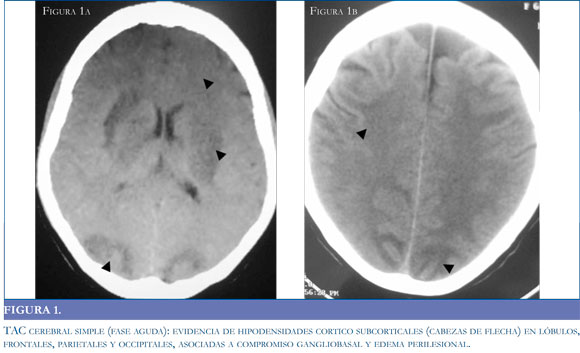

La tomografía puede no ser el método de elección en consideración a sus características operativas, pero es un recurso de fácil acceso para la aproximación diagnóstica. Si bien la tomografía puede ser negativa en la etapas tempranas del síndrome (39), está documenta la presencia de lesiones hipodensas habitualmente simétricas1 en la sustancia blanca de los territorios posteriores y gangliobasales (34) (Figuras 1 a y b); con el desenlace clínico de la patología, las imágenes tomográficas muestran una resolución de las hipodensidades descritas en el momento de mayor intensidad clínica (Figuras 2 a y b).